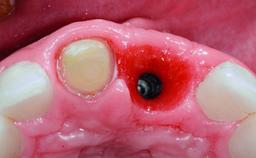

Replacement of an Upper Right Central Incisor with Root Resorption: Ridge Preservation, Delayed Placement of an NC Bone Level Roxolid Implant

A 32-year-old female Caucasian patient with a compromised maxillary right central incisor was referred to us by a general dentist. Her chief complaints were discomfort and mobility of tooth 11 with unsatisfactory esthetics due to discoloration. The patient reported a previous trauma, some years earlier, as the origin of pathology on the afflicted tooth. Anamnesis was negative for any other dental or periodontal pathology in the remaining dentition. The patient did not take any medication and reported to be a light smoker (5–10 cigs/day). She had high esthetic expectations of her treatment. The extraoral examination revealed a high smile line with full exposure of her maxillary teeth and surrounding soft tissue in the area between the second premolars.

# of Implants 1

Type of Implants Reduced-Diameter|Two-Piece

Placement Protocol Early or late implant placement